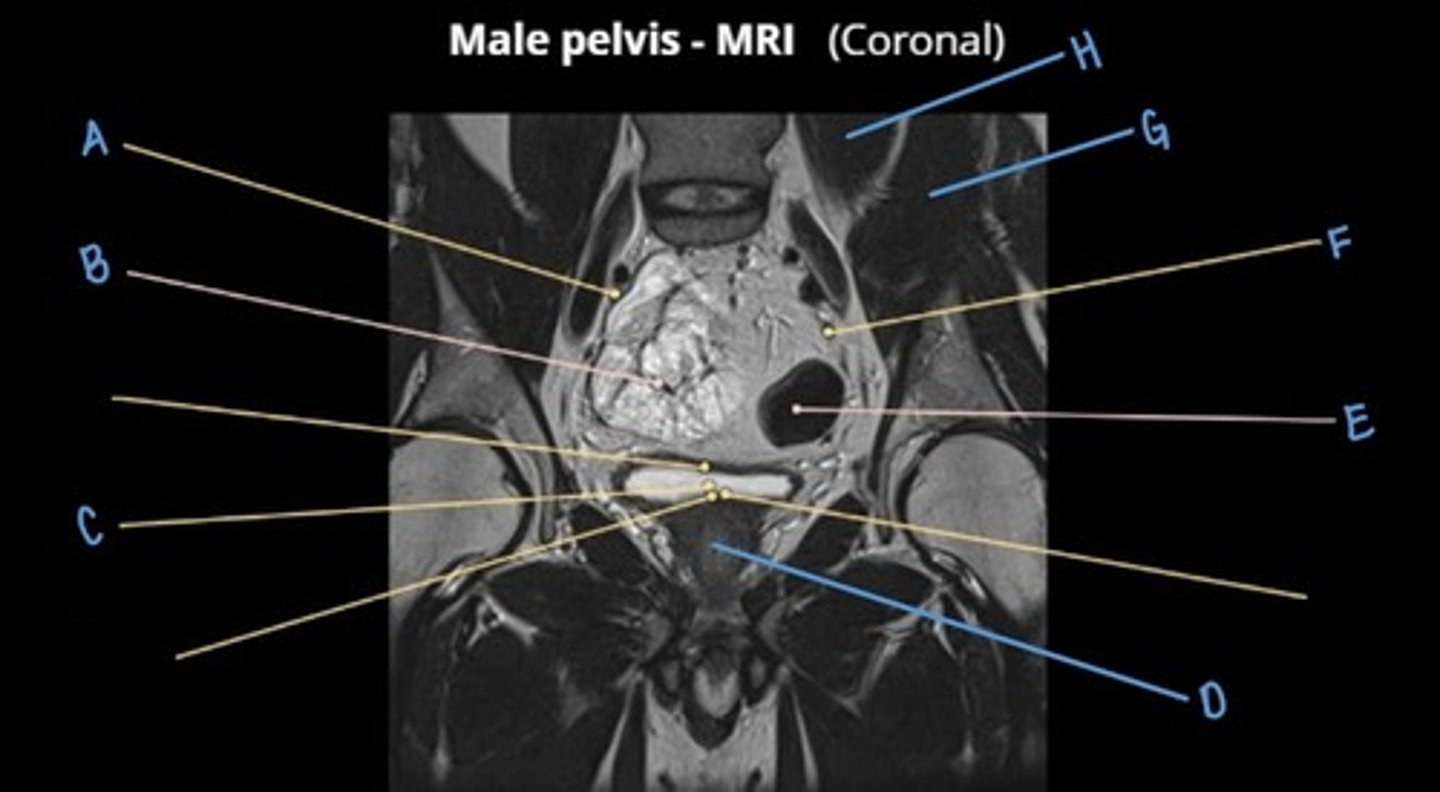

obturator externus muscle

A

obturator internus muscle

B

levator ani muscle (pubic diaphragm)

C

gluteus maximus muscle

D

pubic symphysis

E

rectus abdominus muscle